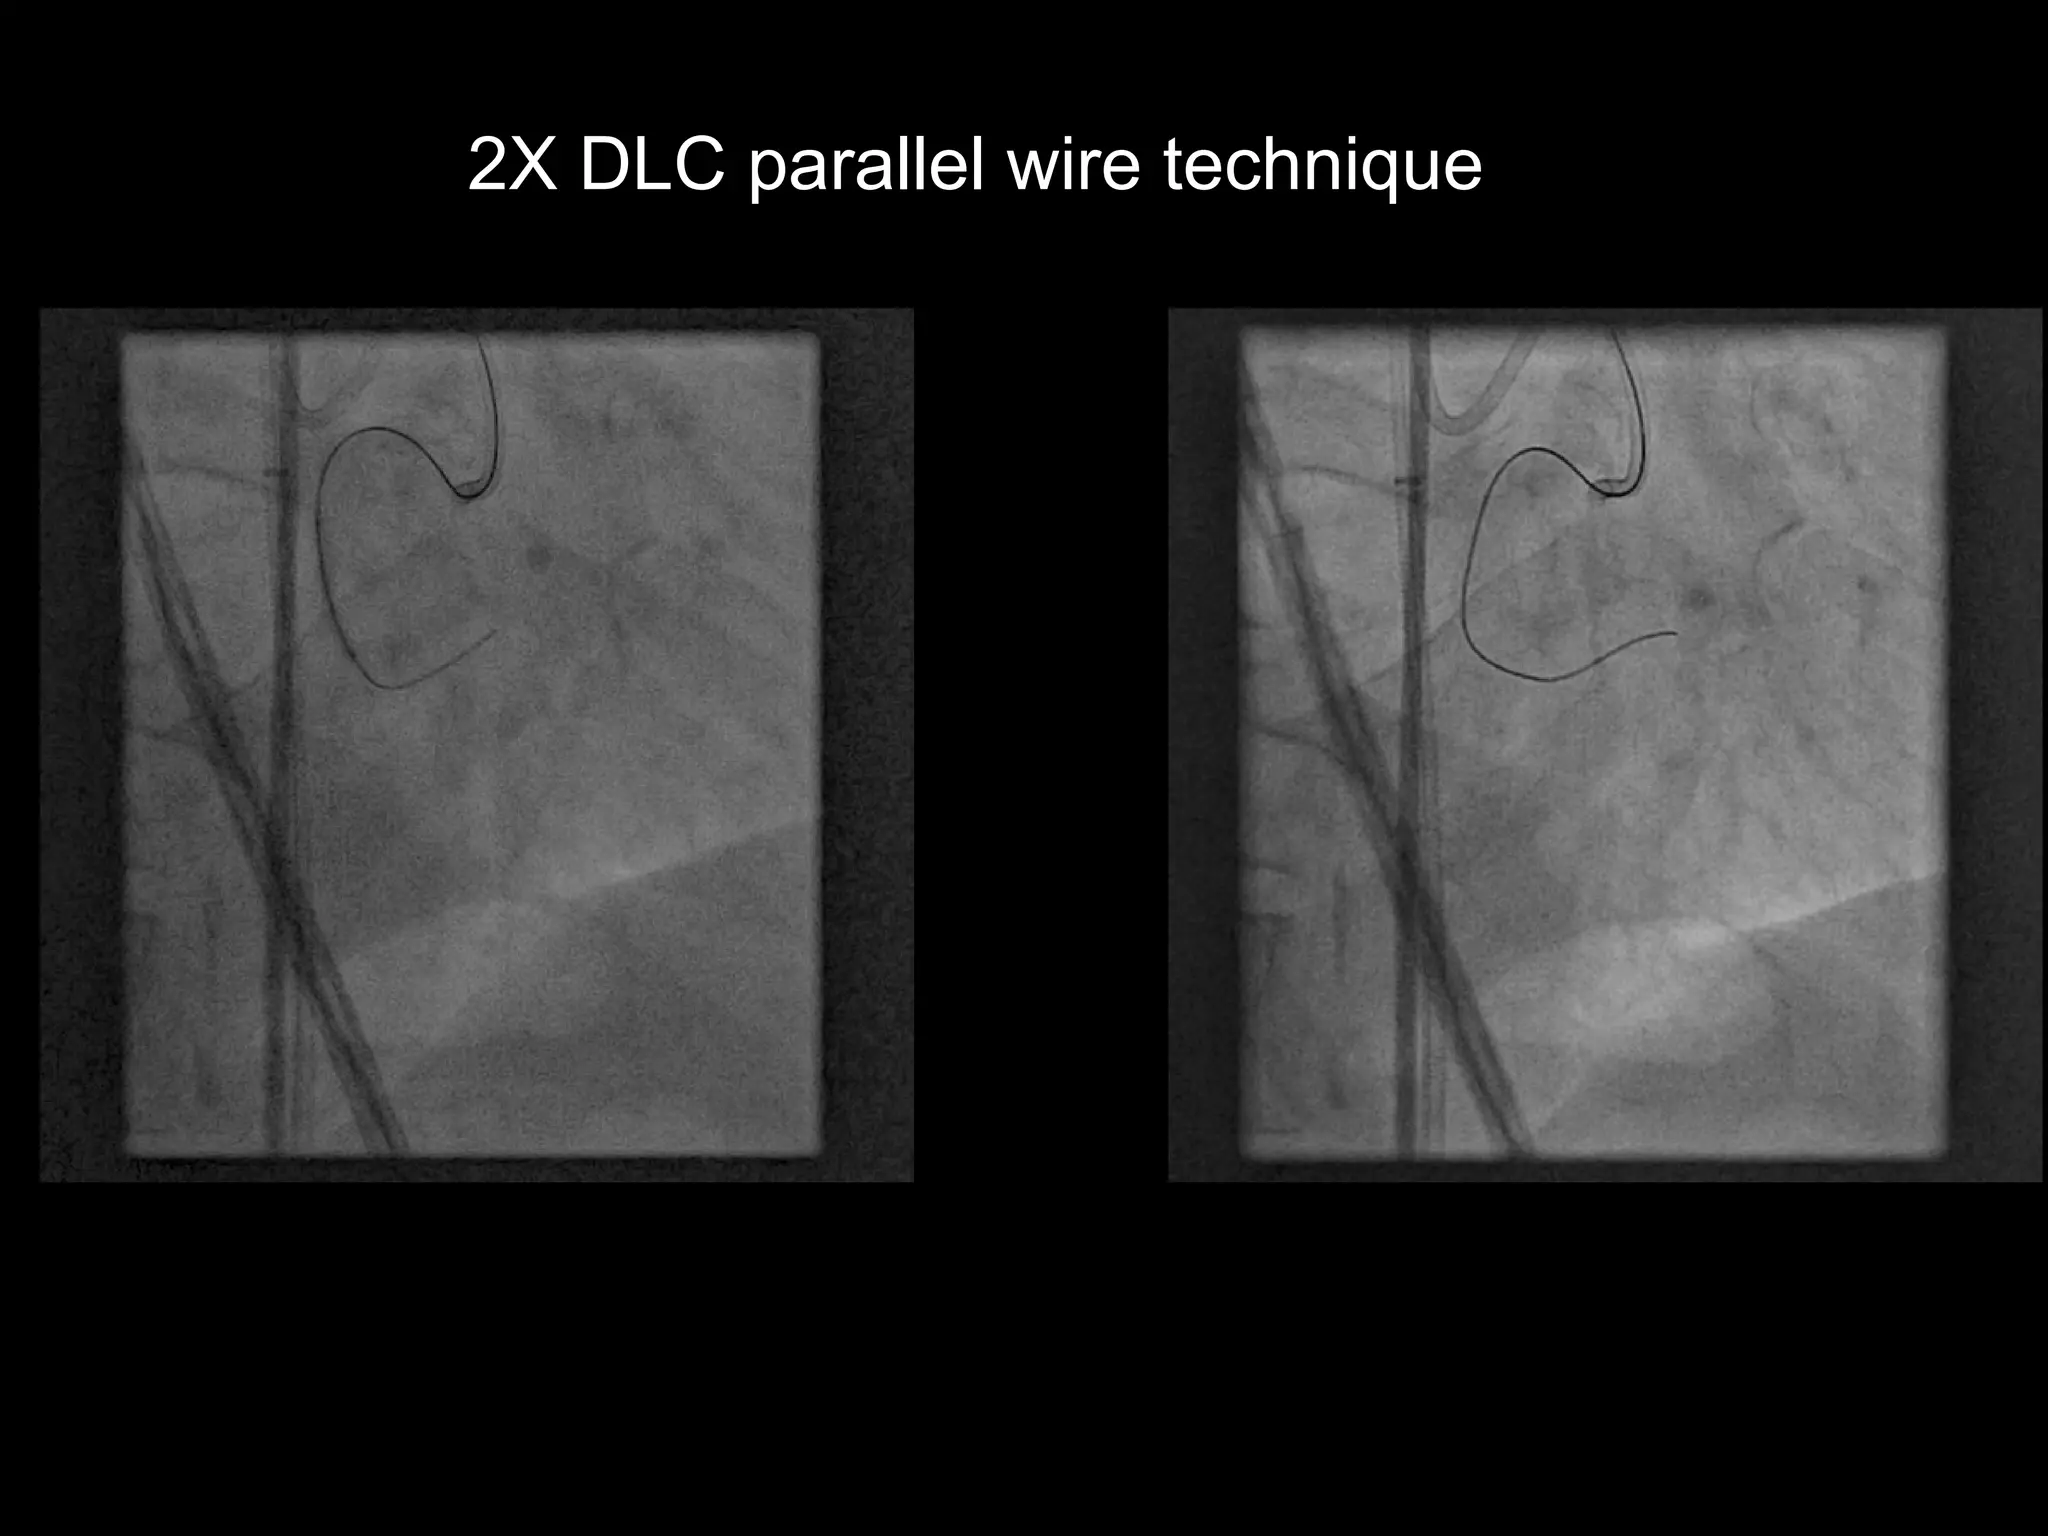

2X DLC parallel wire technique